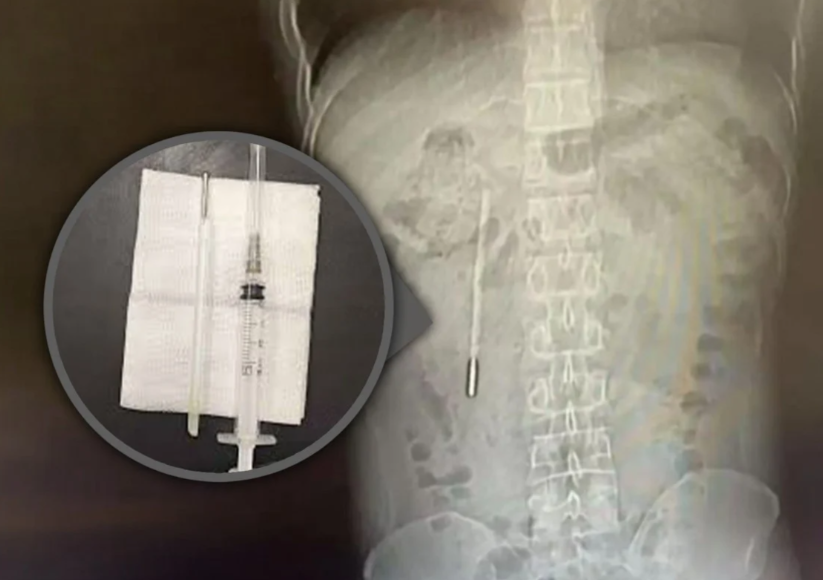

Хирургам потребовалось 20 минут, чтобы извлечь инородное тело.

Хоть маркировка на найденном градуснике стёрлась, сам он был цел.